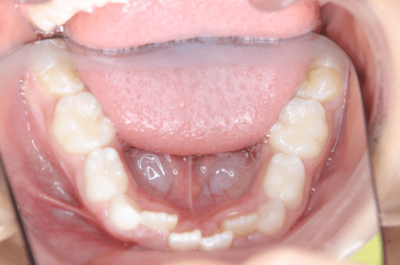

2.小学生に行う矯正治療とは?

小学生に行う矯正治療の主な目的

- 顎の成長を促進 or 抑制

- 歯列弓の拡大

- 悪習癖の改善

この時期のお子さまの矯正治療は、取り外し可能な装置も使いますし、接着剤で付ける外せない装置も使います。使用する矯正装置は歯並びのタイプは様々に異なるため、同じ人はいませんので、同じ年齢や似たような状態に見えても違う装置を使うことがあります。装置の種類はある程度ご希望に添うことができますから、相談してください。

お子さまはどんな歯並びですか?

3.叢生(そうせい)、でこぼこ

叢生とは、歯並びがデコボコの状態のことを指します。